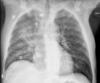

RN a termo.

Cardiomegalia massiva em um neonato com pulmão normal (sem edema alveolar ou intersticial, sem derrame pleural)

Cardiomiopatia neonatal.